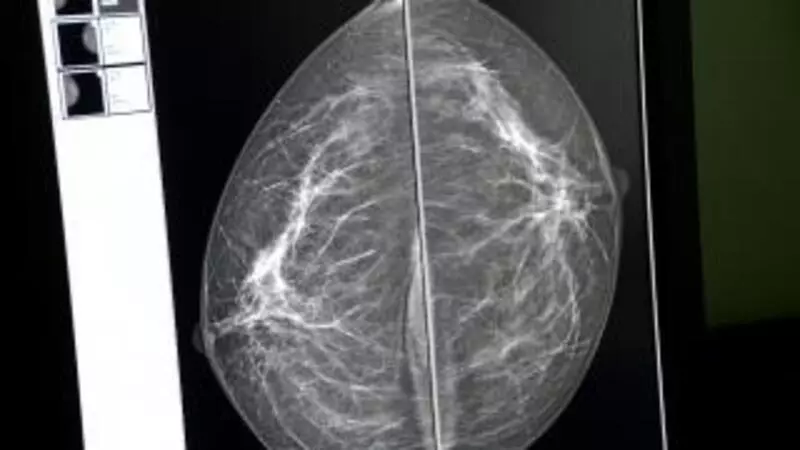

Сахалинок приглашают на обследование к маммологу

Жительниц Сахалинской области приглашают на обследование груди.

Как стало известно РИА «Сахалин-Курилы», 7 октября в госучреждениях здравоохранения области состоится день открытых дверей, приуроченный к Всемирному дню борьбы с раком молочной железы. На прием к специалистам с целью выявления опухолевых заболеваний молочной железы приглашаются женщины старше 35 лет, не состоящие на учете у онколога.

Прием будет проходить с 09:00 до 15:00, предварительная запись осуществляется в поликлиниках. Обследование бесплатное, при наличии паспорта, медицинского полиса, СНИЛС. Желательно иметь при себе данные маммографии и УЗИ-диагностики, сделанные ранее (при наличии) – для сравнительного анализа, информирует пресс-служба регионального минздрава.